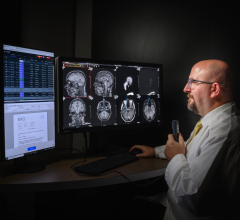

The ImageGrid Mammography Web Viewer and Radiology Web Viewer are diagnostic tools aiming for timely access to medical imaging studies from anywhere and at any time to improve patient care. Both viewing applications are highly scalable and designed to

accommodate multiple concurrent users without the need to invest in additional servers, said the company. As a multi-modality visualization solution, the viewers allow radiologists to view all relevant prior studies from one workstation.

For hospitals with specialty imaging departments, the ImageGrid RIS/PACS Appliance provides immediate access and diagnostic viewing capabilities from any workstation on the network. As a thin-client application, the ImageGrid Web Viewers do not require installation of costly software on every workstation on the network or at a physician’s remote workstation.